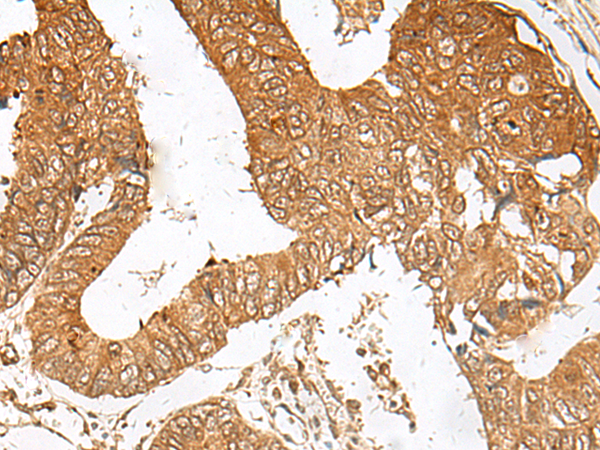

IHC positive control:

Human cervical cancer and Human thyroid cancer

IHC Recommend dilution:

50-300